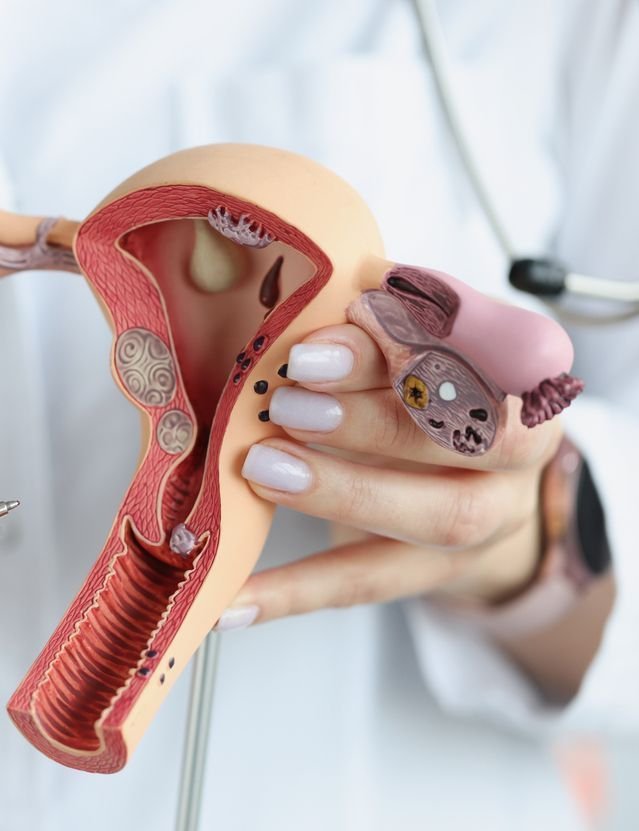

Gynecology

Advanced gynecology care providing diagnosis, treatment and surgical solutions for comprehensive women’s health and reproductive wellness needs.